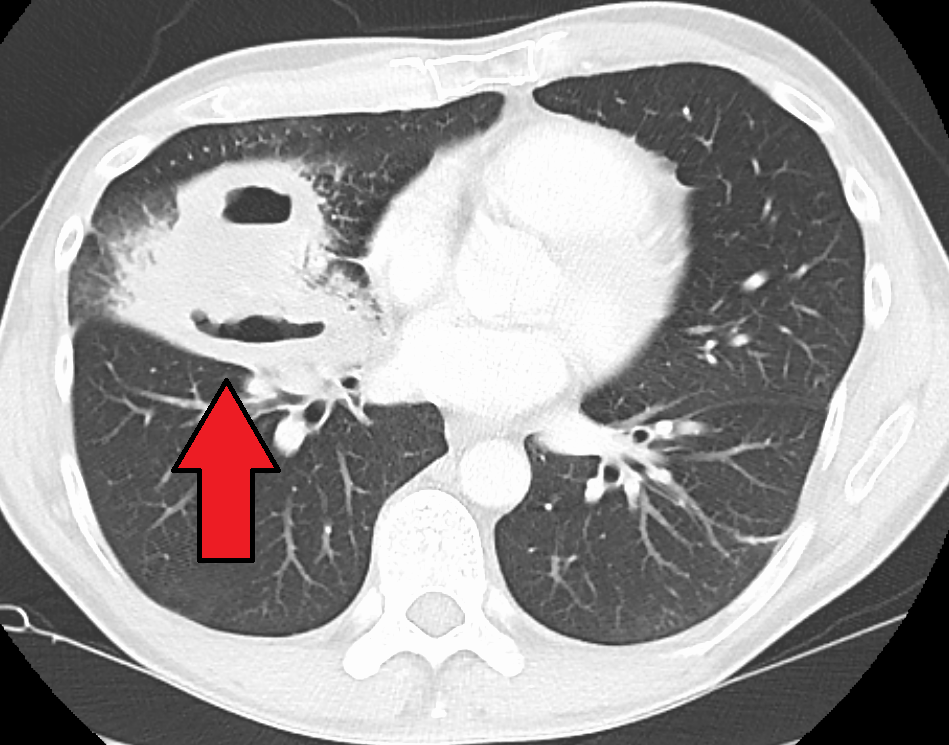

폐 잡음은 특별한 것은 없다. 흉부 엑스레이에서 폐 부분에 단발성 구형 백색 음영이 관찰되며, 구형 음영 내부는 고름으로 채워져 있어 수평선이 관찰될 수 있다. CT 스캔으로 확진할 수 있다.[1]

5. 1. 영상 검사

폐농양은 종종 편측에 나타나며, 누워있을 때 중력에 의해 영향받는 상엽의 후방 분절과 하엽의 첨단 분절을 침범하는 단일 병변이다. 공기-액체 경계면(air-fluid level)의 존재는 기관지로의 파열이나 드물게 가스 형성 미생물의 성장을 의미한다.[1]흉부 엑스레이에서는 폐 부분에 단발성 구형 백색 음영이 관찰된다.[1] 구형 음영의 내부는 고름으로 채워져 있으며, 수평선이 관찰될 수 있다.[1] CT 스캔으로 확진할 수 있다.[1]

폐 잡음은 특별한 것은 없다. 흉부 엑스레이에서 폐야에 단발성 구형 백색 음영을 관찰한다. 구형 음영의 내부는 고름으로 채워져 있으며, 수평선을 관찰할 수 있다. CT 스캔으로 확진할 수 있다.